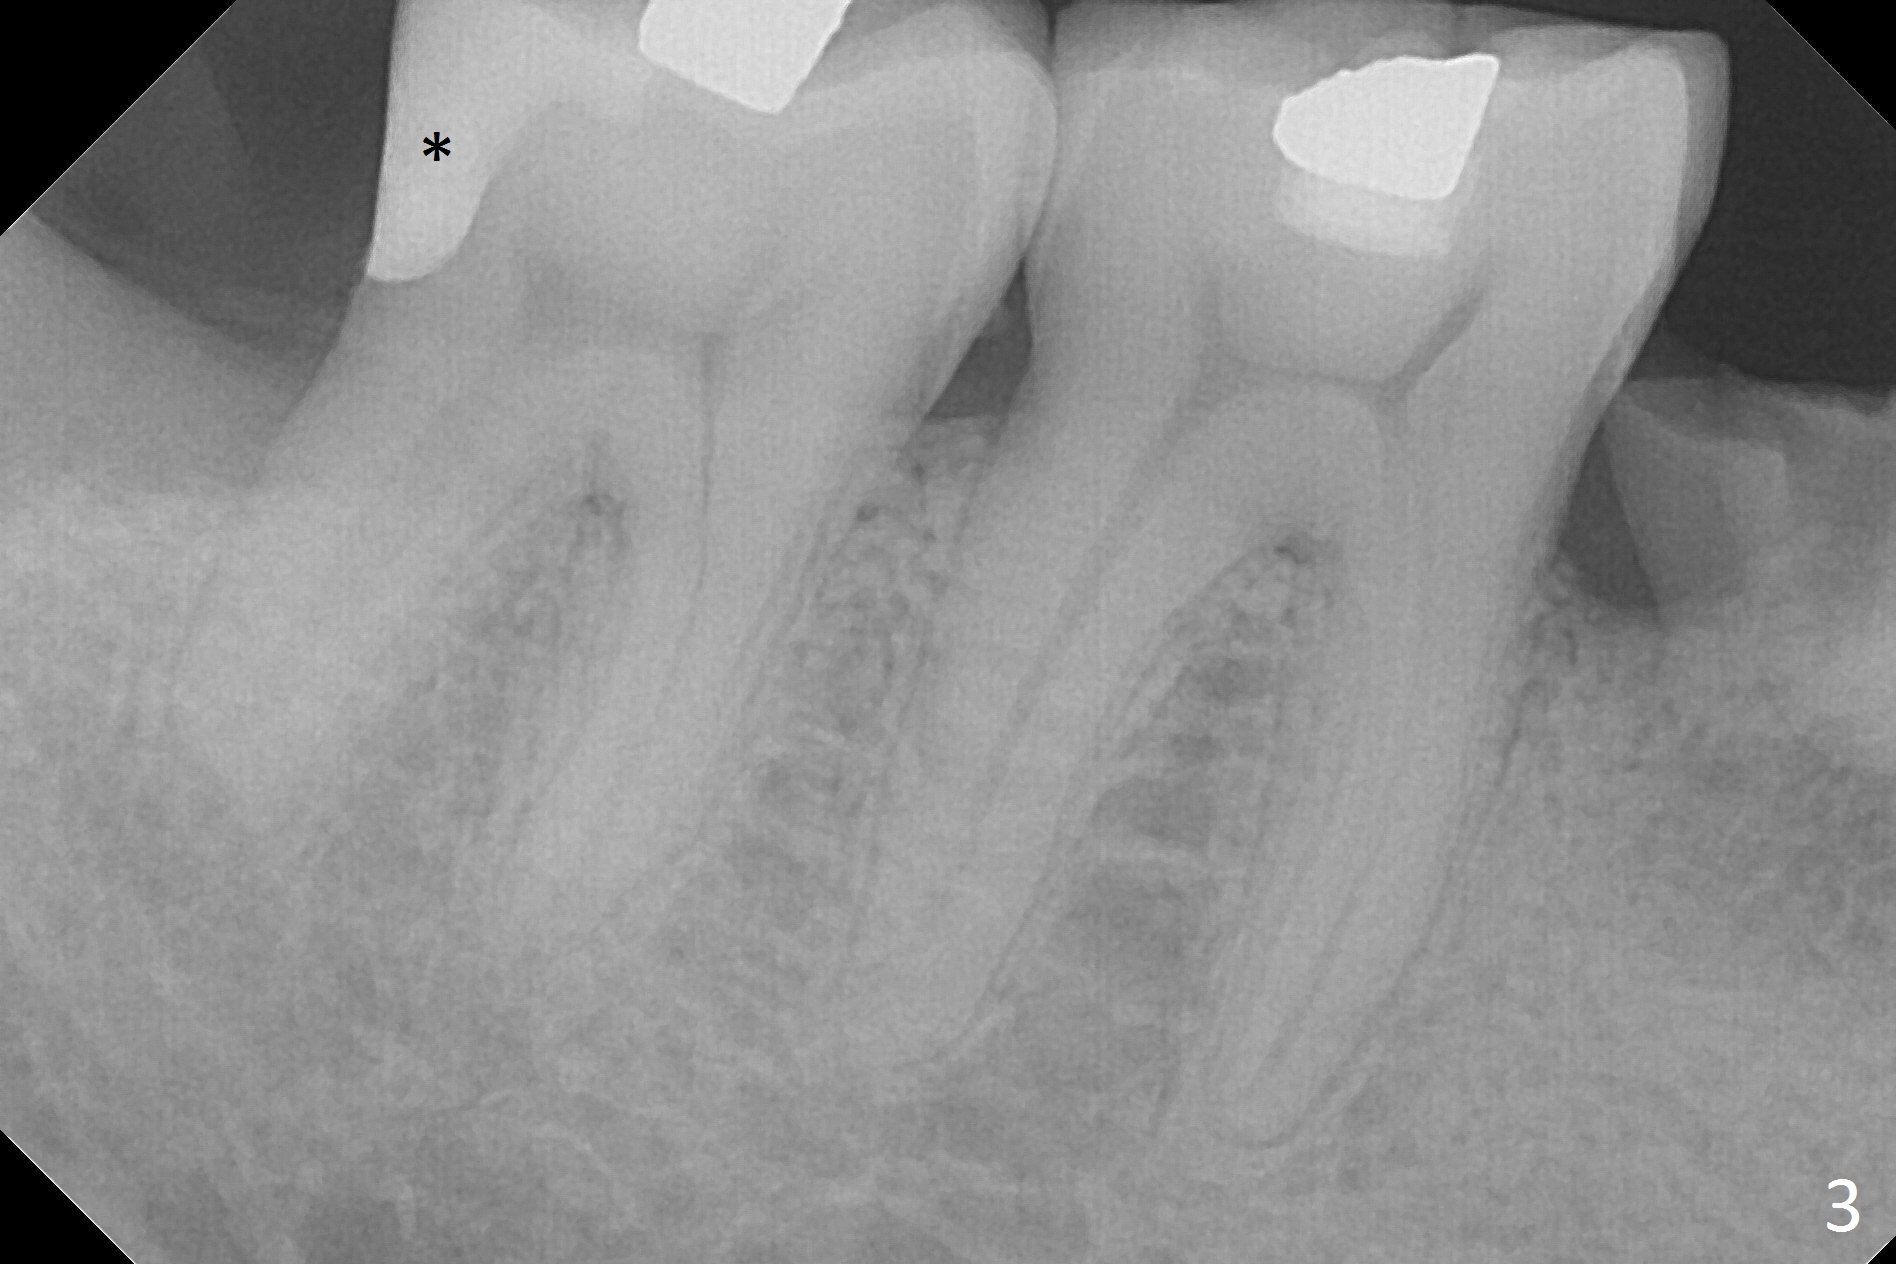

Resin restoration of the distal cervical caries of the lower 2nd molar (Fig.1 <) is usually performed when the extraction socket of the 3rd molar heals. It is difficult to remove the most cervical portion of the caries. The healed gingiva may be friable and easily hemorrhagic.

When the tooth #32 of a 47-year-old man is extracted, two pieces of 2x2 gauze (Fig.2 G) are inserted into the wound for hemostasis and composite is placed at #31 without compromise (Fig.2,3 *). Finally a 20x10 mm collagen plug is inserted into the socket of #32 prior to suturing to prevent Dry Socket. There is no leak or 2nd caries 1 year postop (Fig.4).